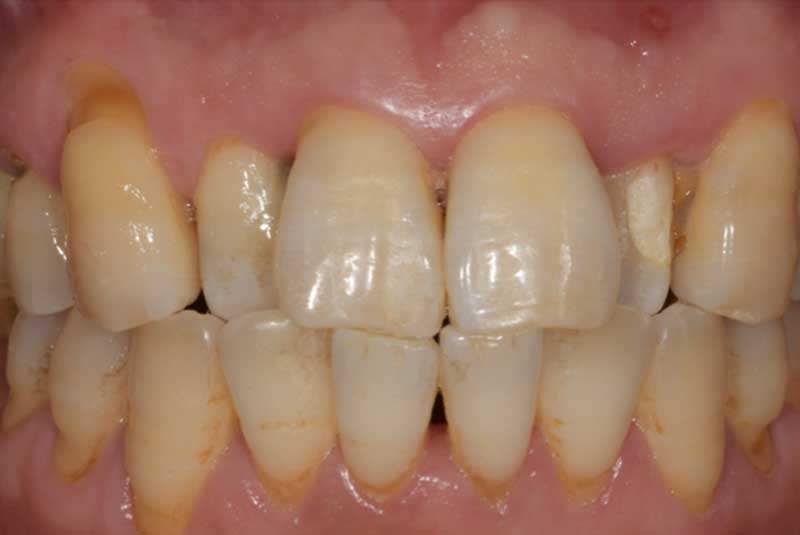

All on 6: Facial cut back (PFZ) Zirconia Full arch prosthesis for Maxilla and Mandible Before & After

The patient had her implants placed 20 years ago. Four implants, particularly in the maxilla, were not positioned ideally for me to utilize and restore, while the four implants in the mandible were outdated and no longer functional. The patient's primary concern is to restore both function and aesthetics.